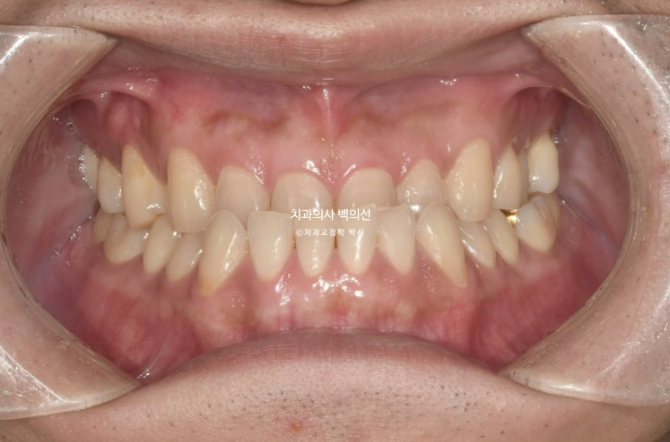

23년 7월 앞니 거꾸로 물림을 교정으로 해결하고자 내원하신 30대 남성분

아랫니에 가려서 잘 보이지는 않지만

앞니 마모가 상당히 심합니다.

거꾸로 물리는 상태로 오래 지내오다보니, 아랫니와 닿는 부분들이 마모가 된 것입니다.

마모도를 보면 교합력도 상당히 센 편임을 알 수 있습니다.